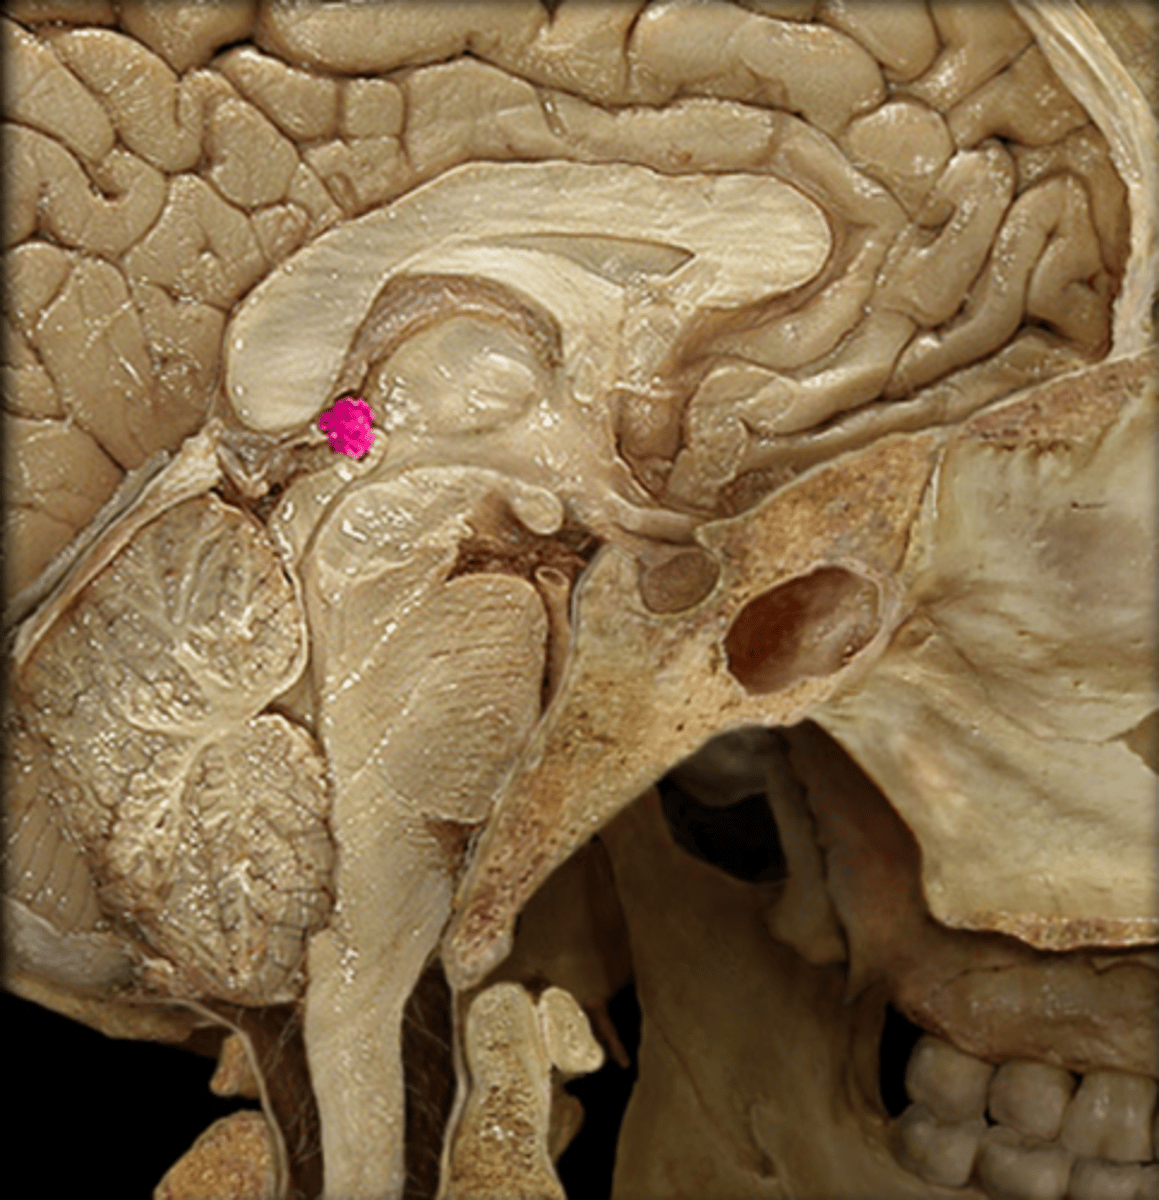

Hypothalamus and Pineal Gland Anatomy & Physiology II Lab (Hypothalamus & Pineal Gland: Dissection & Notes) Endocrine System

hypothalamus

hypothalamus

What structure is commonly known as the "master organ" of the endocrine system?

infundibulum

The narrow stalk that connects the pituitary gland to the hypothalamus is called the ______________.

infundibulum

This region connects the hypothalamus and the pituitary gland.